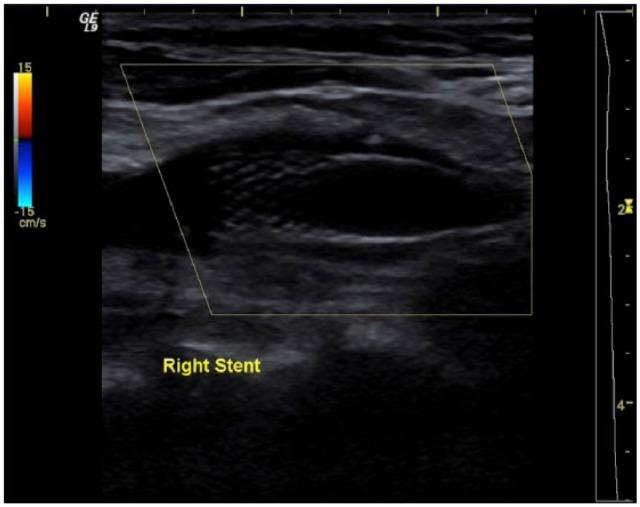

Carotid stump syndrome is defined as the persistence of retinal or cerebral ischaemic events with complete occlusion of the ipsilateral internal carotid artery. The aim of this retrospective cases series was to assess the outcomes for patients with carotid stump syndrome managed with surgical intervention. A series of 11 cases of carotid stump syndrome in nine patients presented to our tertiary vascular centre from October 2004 to February 2016. Indications for intervention were amaurosis fugax, transient ischaemic attacks and stroke. In total, 11 procedures were performed on nine patients including carotid angioplasty and stenting or carotid endarterectomy with patching. The mean follow-up period was 56.6 months. One patient suffered a myocardial infarction 30 days, post-operatively, and one patient was lost to follow-up. In the remaining seven patients, there was a complete resolution of symptoms. There were no incidents of death, stroke, cranial nerve injury, wound haematoma or procedural bleeding. Surgical exclusion of carotid stumps combined with dual antiplatelet agents was found to be a safe and effective treatment method for carotid stump syndrome.

颈动脉残端综合征的定义为同侧颈内动脉完全闭塞时视网膜或脑部缺血事件持续存在。本回顾性病例系列的目的是评估接受手术干预治疗的颈动脉残端综合征患者的治疗效果。2004年10月至2016年2月期间,9例患者中的11例颈动脉残端综合征病例被送至我们的三级血管中心。干预指征为一过性黑矇、短暂性脑缺血发作和中风。总共对9例患者进行了11次手术,包括颈动脉血管成形术和支架置入术或颈动脉内膜切除术加修补术。平均随访期为56.6个月。1例患者术后30天发生心肌梗死,1例患者失访。其余7例患者症状完全缓解。未发生死亡、中风、颅神经损伤、伤口血肿或手术出血事件。发现手术切除颈动脉残端联合双联抗血小板药物是治疗颈动脉残端综合征的一种安全有效的方法。